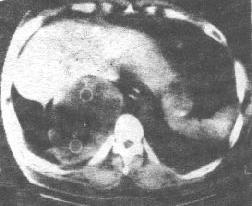

胸部X線片、胸部CT和MRI檢查等。胸部X線檢查腫瘤多位於後縱隔脊柱旁,邊界清楚,密度均勻之圓形或卵圓形緻密陰影,多為單側單發。胸部CT能顯示腫瘤大小、部位以及胸壁、縱隔受侵的程度,也可顯示腫瘤通過肋間隙或椎間孔呈啞鈴形的形態。